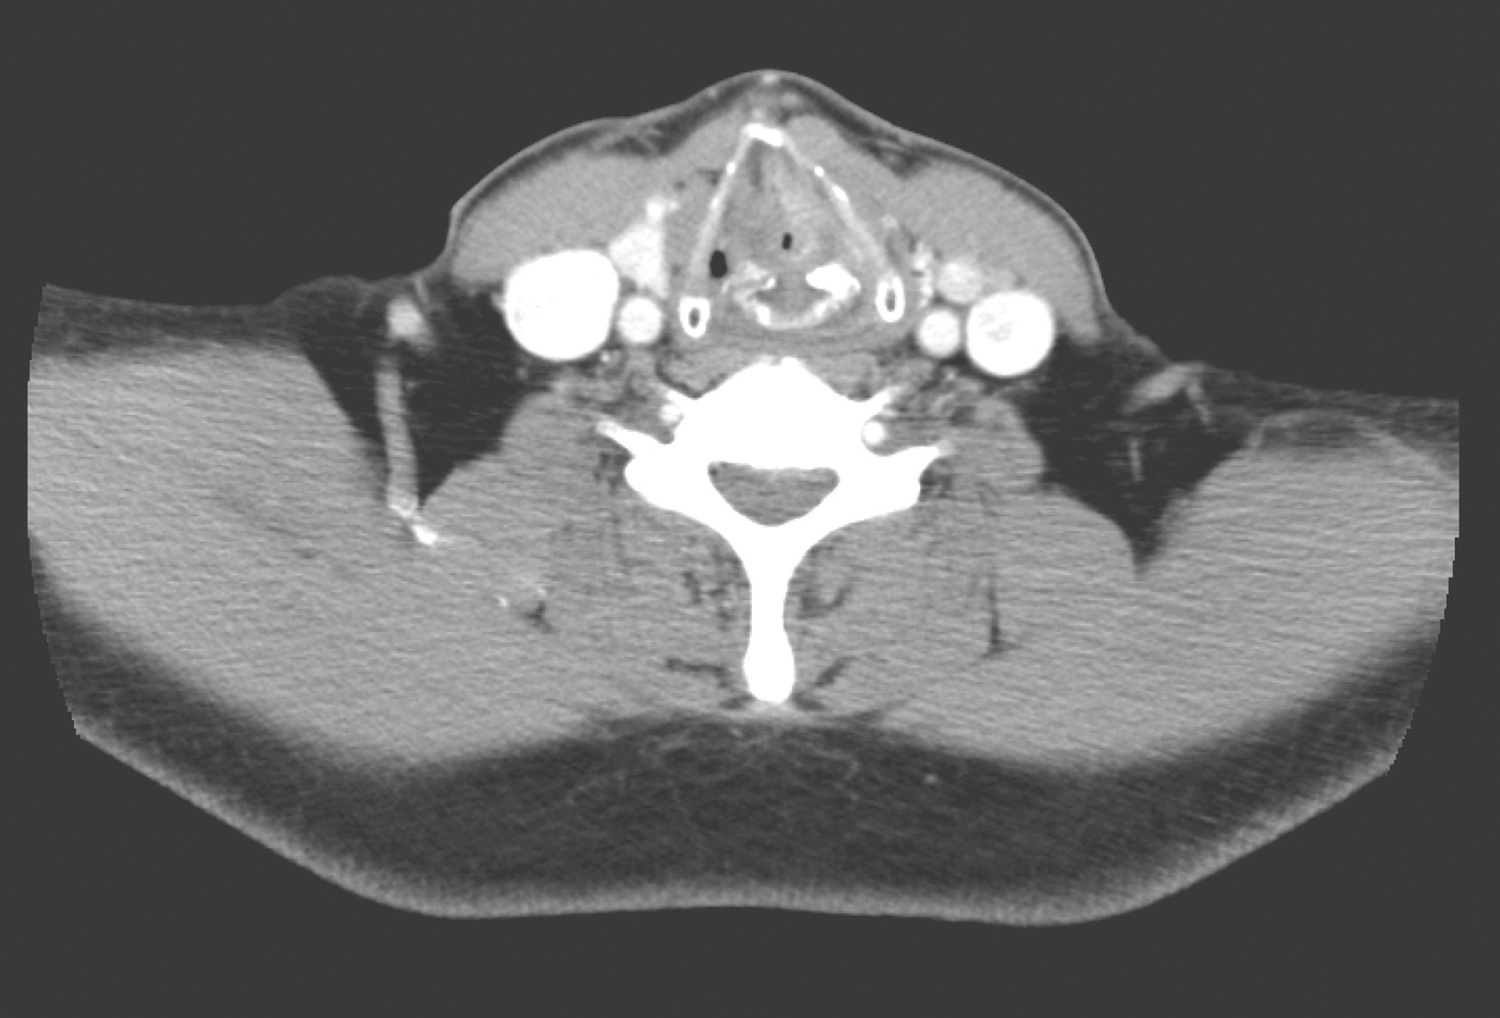

1小时条评论59岁男性患者,声音嘶哑半年余,病因何在? 【病例简介】 患者男性,59岁。因声音嘶哑半年余于2017年4月10日收入头颈外科。半年前患者无明显诱因出现声音嘶哑,当地医院就诊给予中药治疗,声嘶症状稍缓解;近期外院鼻咽喉镜,发现喉内肿物,活检病理为(右声...